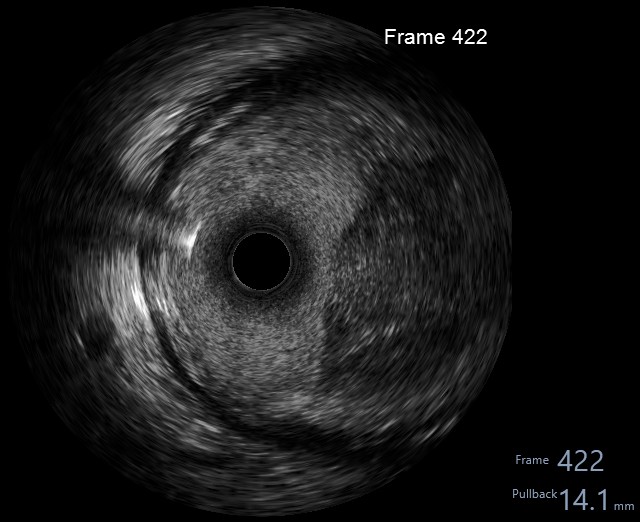

Index procedure:Right radial access with SAL 0.75/6F guide and 6F guide extension catheter. Wiring succeeded with Fielder XTR. Sequential predilation with 2.5/15 mm SC balloon, followed with aspiration thrombectomy & intracoronary injections of tirofiban & fasudil via the thrombectomy catheter. Evaluation angiography showed residual large thrombus burden. IVUS catheter had a significant bias due to the large vessel calibre, it could only reach as far as distal RCA. IVUS revealed heavy burden of consolidated thrombus in distal RCA with diffuse ectasia. Predilation with 3.0/15 mm NC balloon and further intracoronary injections of tirofiban via guide catheter still produced a significant residual thrombus burden, albeit with a slightly better distal flow. Deferred stenting and put the patient on anticoagulant on top of DAPT.

Repeat procedure:Repeat procedure was performed 2 weeks after the index procedure. We used right radial access with AL 0.75/7F guide and 7F guide extension catheter. Angiography revealed TIMI 2 flow to distal RCA, residual stenosis at distal RCA, residual haziness suggestive of thrombus in PDA. IVUS showed partially recanalized consolidated distal RCA thrombus with acceptable luminal size. ELCA was performed with 1.4 mm ELCA catheter under pure saline infusion technique followed by PCI (2.25/29 mm DES) to PDA. Final angiography showed TIMI 3 flow with residual stenosis at distal RCA. FFR LAD 0.84, no further intervention to LAD.